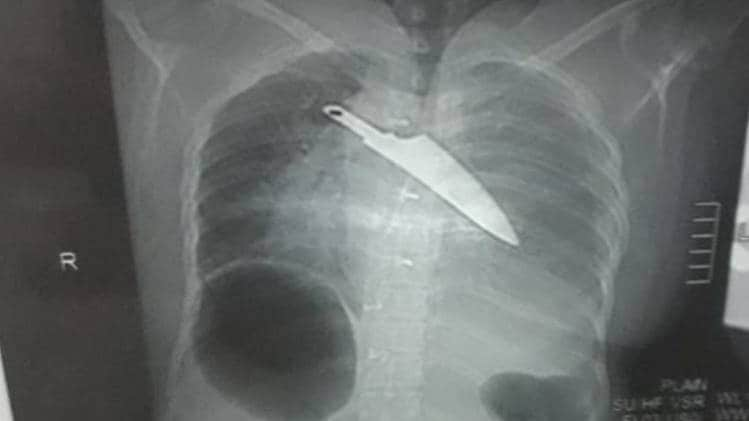

दिल्ली में एक नाबालिग को बाइक स्टंट करने पर टोकना एक शख्स को बहुत महंगा पड़ गया. नाबालिग ने अपने दो साथियों के साथ मिलकर उस शख्स को चाकू से गोद डाला. जिससे उसकी मौत हो गई. डीडीयू अस्पताल के अधिकारी ने बताया कि मृतक पर चाकू से 28 बार वार किए गए थे. उसके शरीर पर गहरे जख्म पाए गए हैं.

मनीष के शव का पोस्टमार्टम करने वाले डॉक्टर के अनुसार मृतक के सीने और धड़ पर गंभीर चोटों के निशान थे, जबकि उसके हाथों और पैरों समेत पूरे शरीर पर कुल 28 जख्म थे, जो चाकू लगने की वजह से हुए थे.